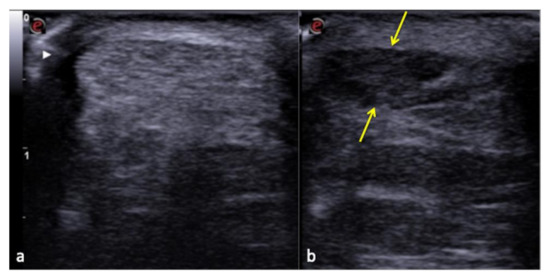

Figure 13. Normal Achilles tendon (a) and anisotropy-related artifact seen at the same tendon (b) that appears hypoechoic (arrows) due to an incorrect angle of the transducer.